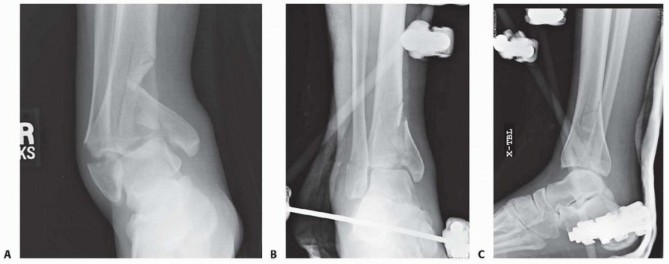

FIG 5 • A-C. Injury and post external fixation films demonstrating an ankle-spanning frame stabilizing a complex pilon fracture.

(continued)

Radiographs of the knee and ankle are necessary to evaluate any articular fracture involvement or associated knee or ankle subluxation or dislocation. Identifying any occult fracture lines aids in the preoperative planning of potential pin placement. Many patients with high-energy tibial fractures have associated foot injuries, and views of the foot and ankle are necessary to identify this injury pattern. Traction radiographs of articular injuries of the tibia are useful to identify the nature and orientation of metaphyseal fragments as well as degree of articular impaction. This aids in determining whether a joint-spanning fixator is necessary. Distraction computed tomography (CT) scans should be obtained

after

the knee- or ankle-spanning fixator has been applied. These studies indicate the effectiveness of the ligamentotaxis reduction. This allows the surgeon to determine the preoperative plan for definitive fixation once the soft tissues have recovered 14 ( FIG 5). 535

### FIG 5 •

D,E. CT scan obtained post distraction in the frame provides valuable information to help determine the preoperative plan for delayed definitive reconstruction once the soft tissues have recovered.